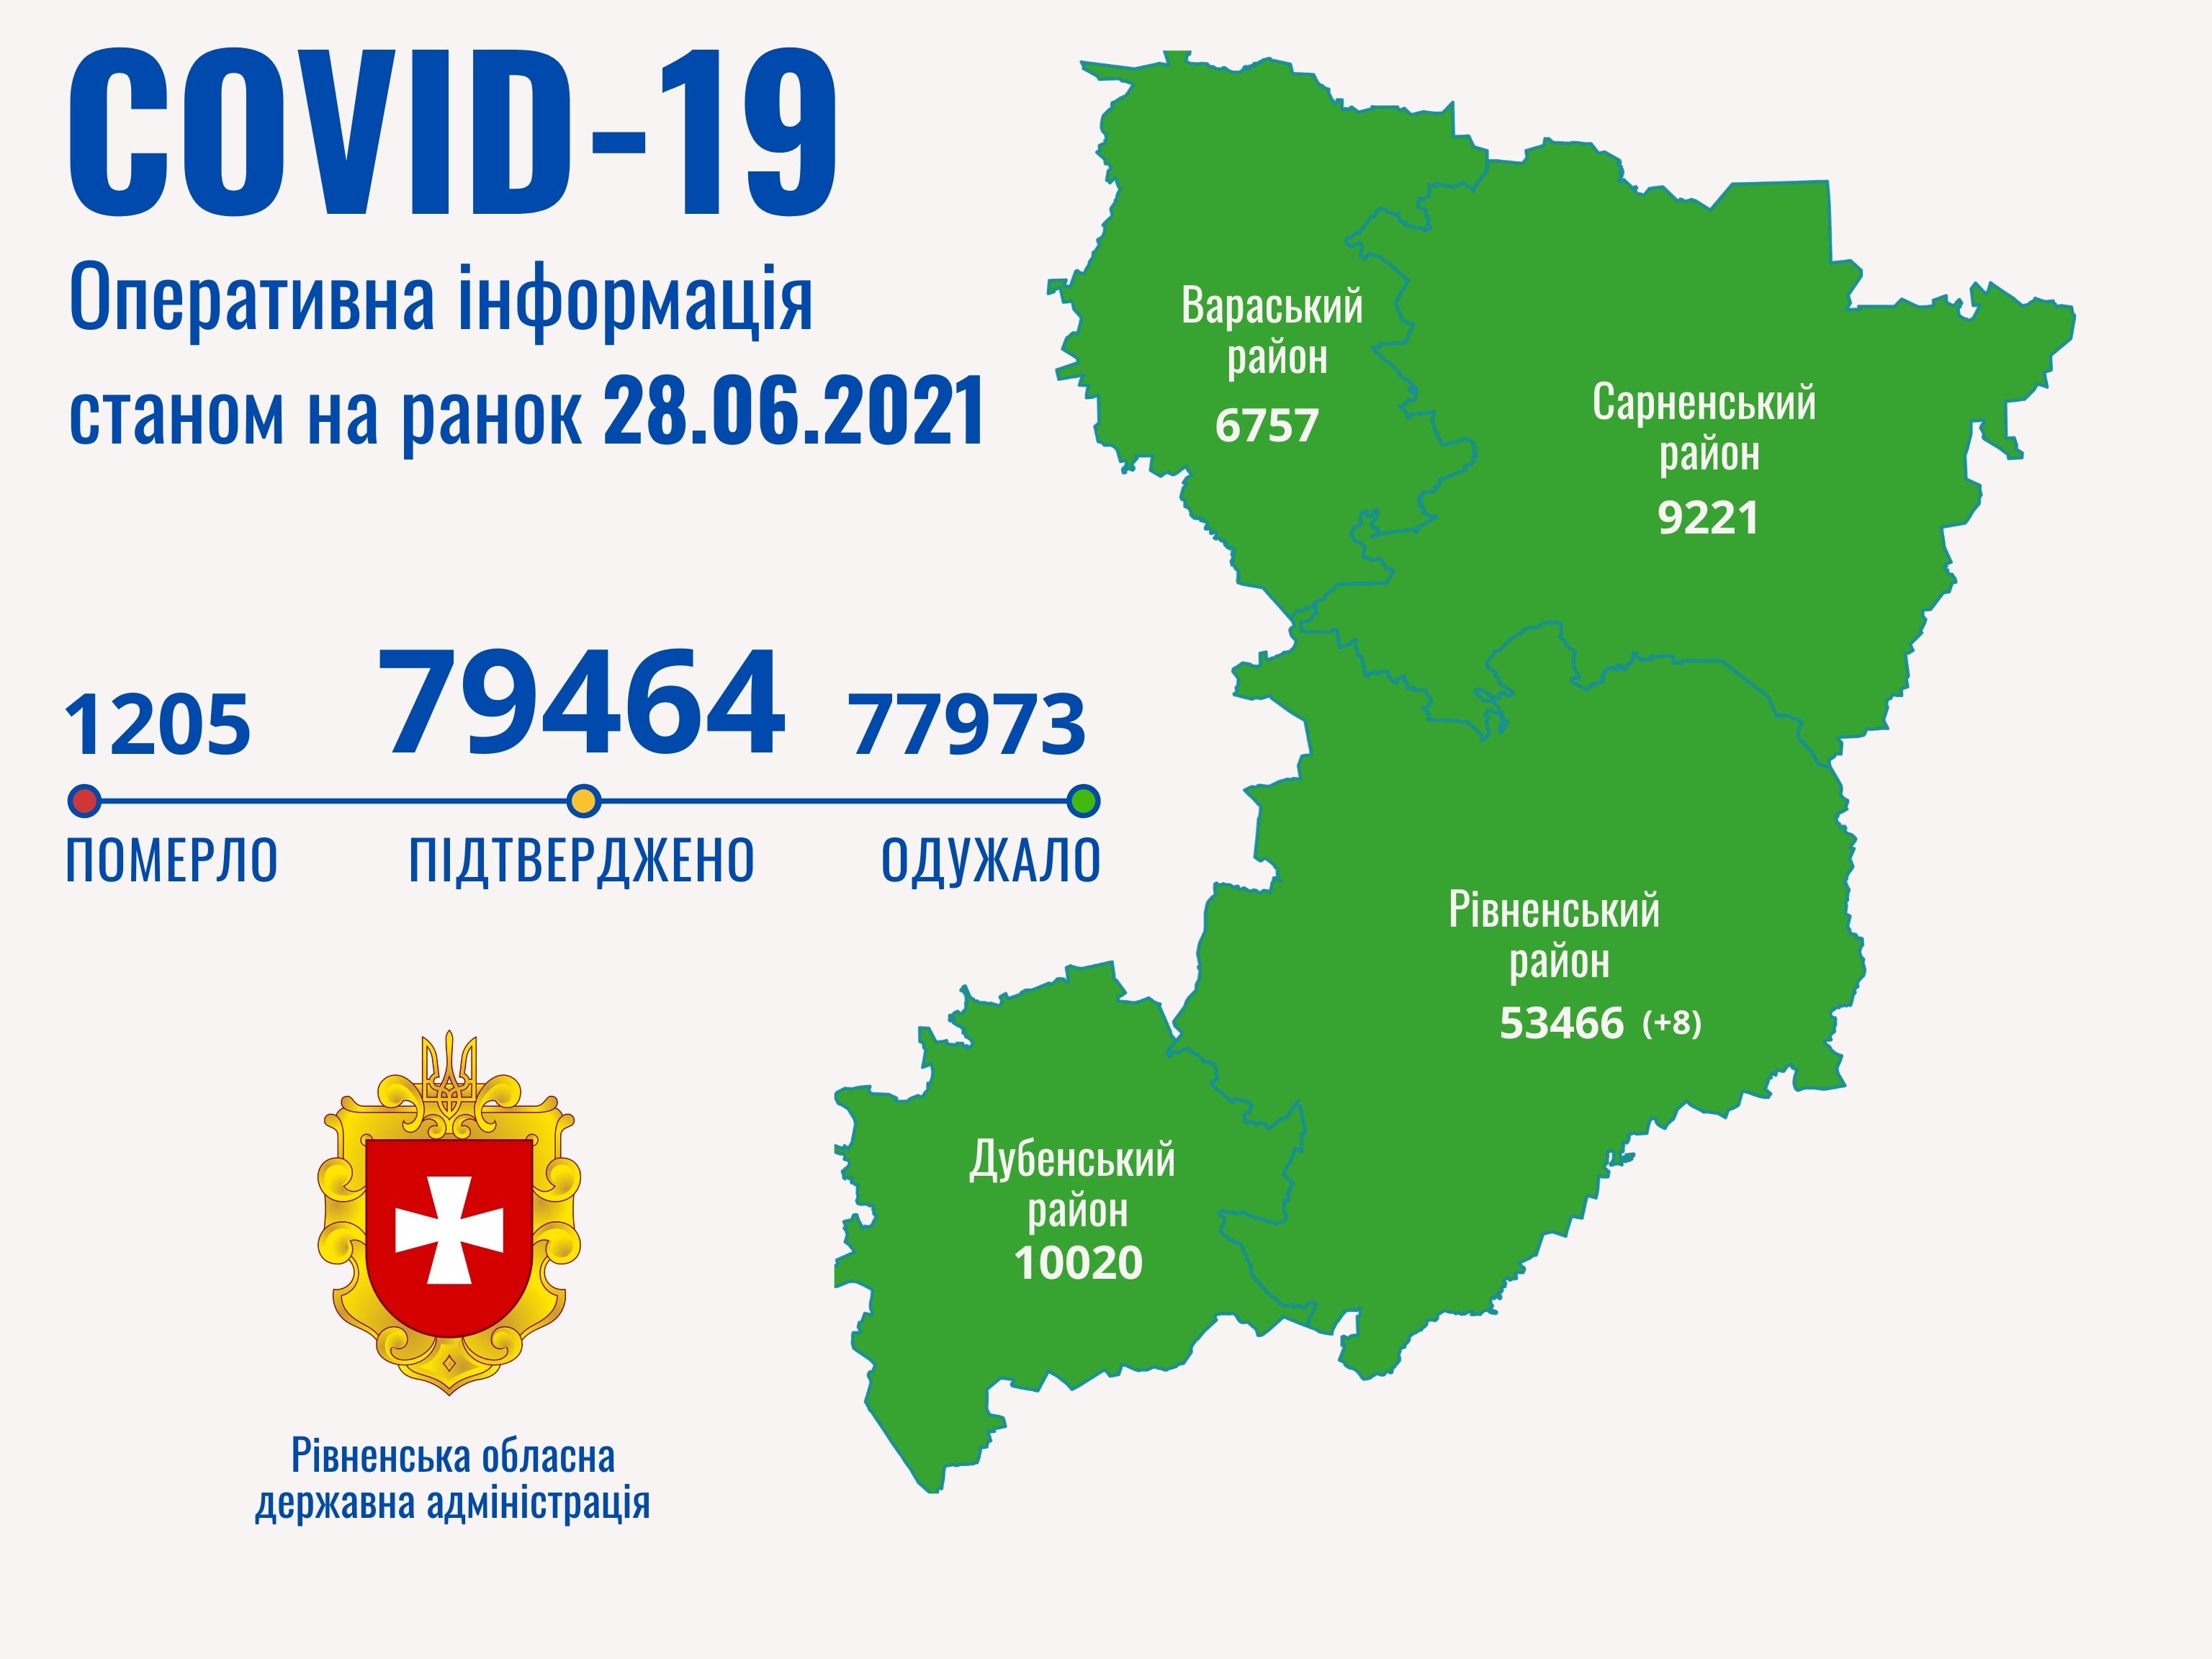

Коронавірус повертається: як стрімко зростає кількість хворих на Рівненщині (ВІДЕО)

Пів тисячі - у важкому стані, 9 жителів Рівненщини померли за добу від коронавірусу